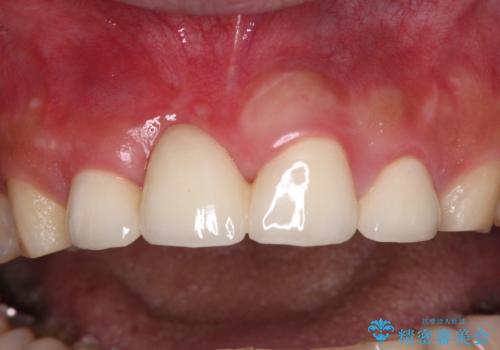

不自然な前歯 歯肉移植を用いた前歯のオールセラミックブリッジ

歯肉移植や根管治療終了後、オールセラミッククラウンおよびブリッジにて補綴することとしました。

歯の幅径のバランスが取れ、自然な口元となりました。